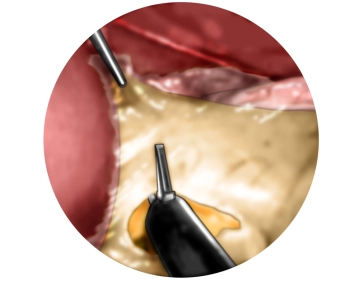

Anspannen des Magen und Inzision des Omentum minus